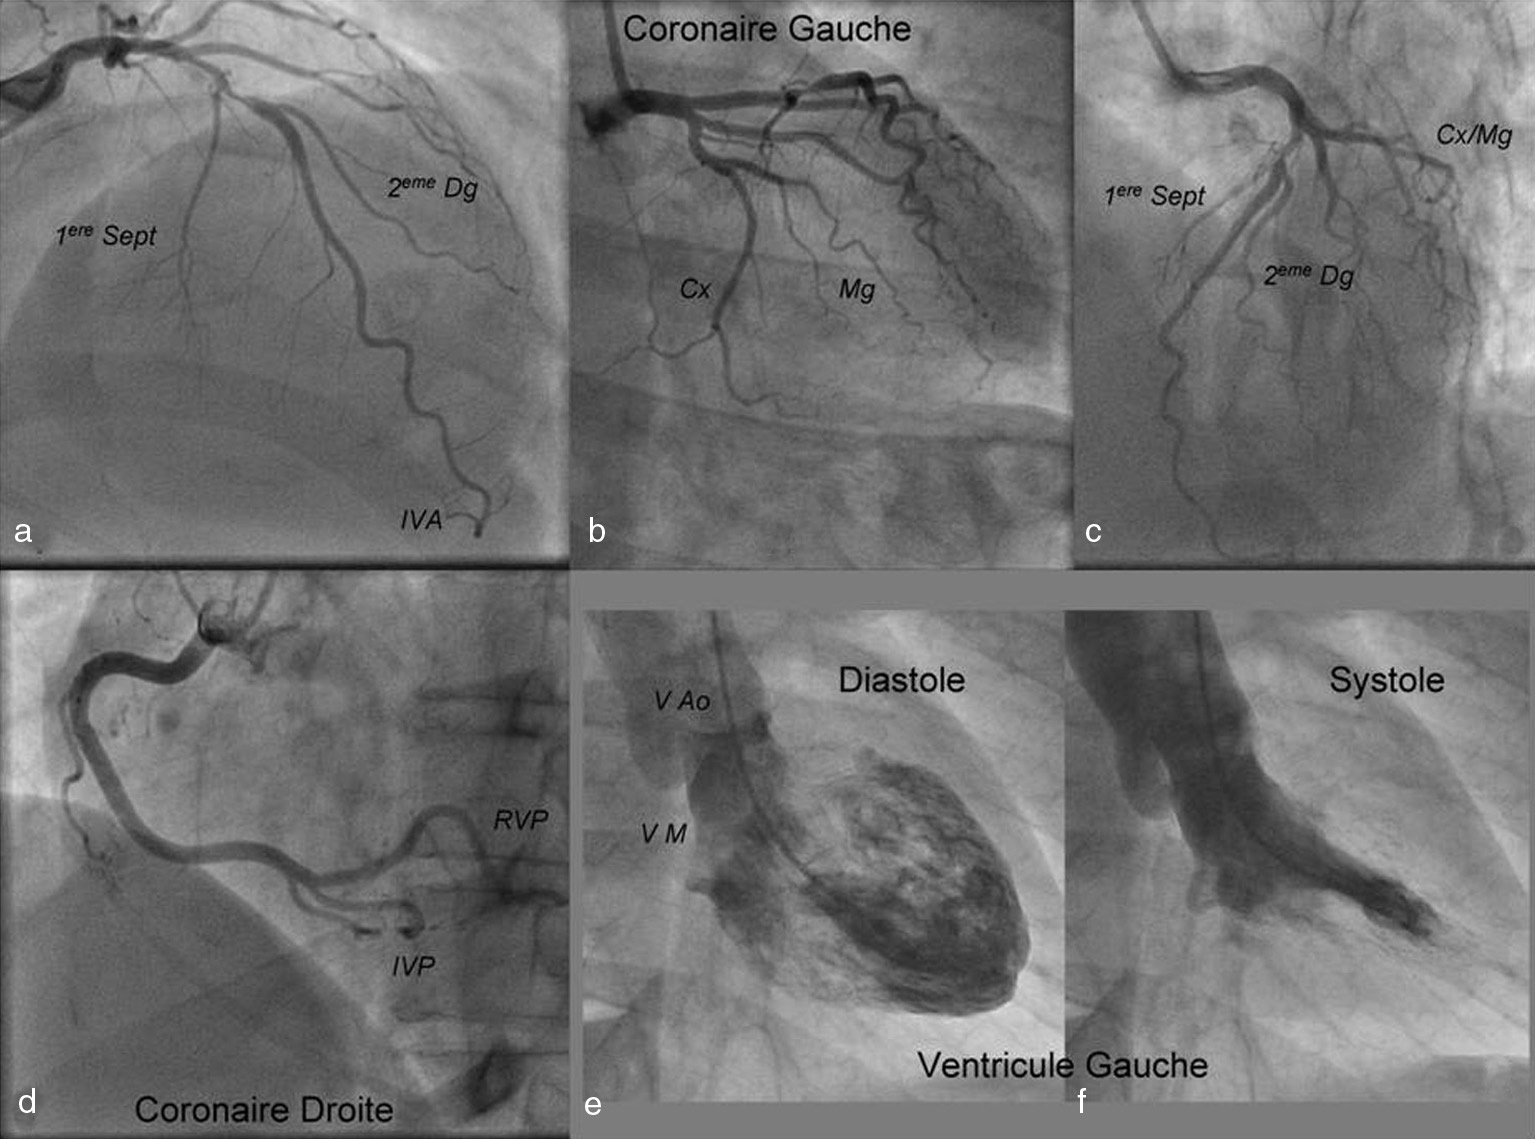

Figure 4. Exemple de coronarographie : opacification du réseau coronaire gauche (a, b, c) ; injection de la coronaire droite (d) ; ventriculographie gauche : diastole (e) et systole (f)

Cx : artère circonflexe ; Dg : artère diagonale ; IVA : artère interventriculaire antérieure ; IVP : artère interventriculaire postérieure ; Mg : artère marginale ; RVP : artère rétroventriculaire ; Sept : artère septale ; VA : valve aortique ; VM : valve mitrale.